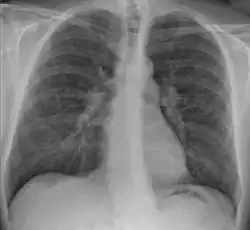

![]() | |

| Chest X-ray showing the typical nodularity of sarcoidosis, predominantly in the hila of the lungs. | |